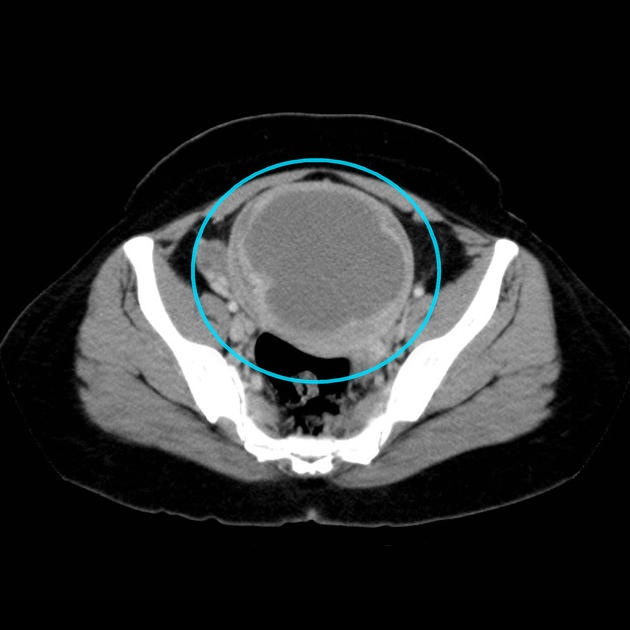

Puzzle 69

Puzzle 69 annotated

What's the Diagnosis?